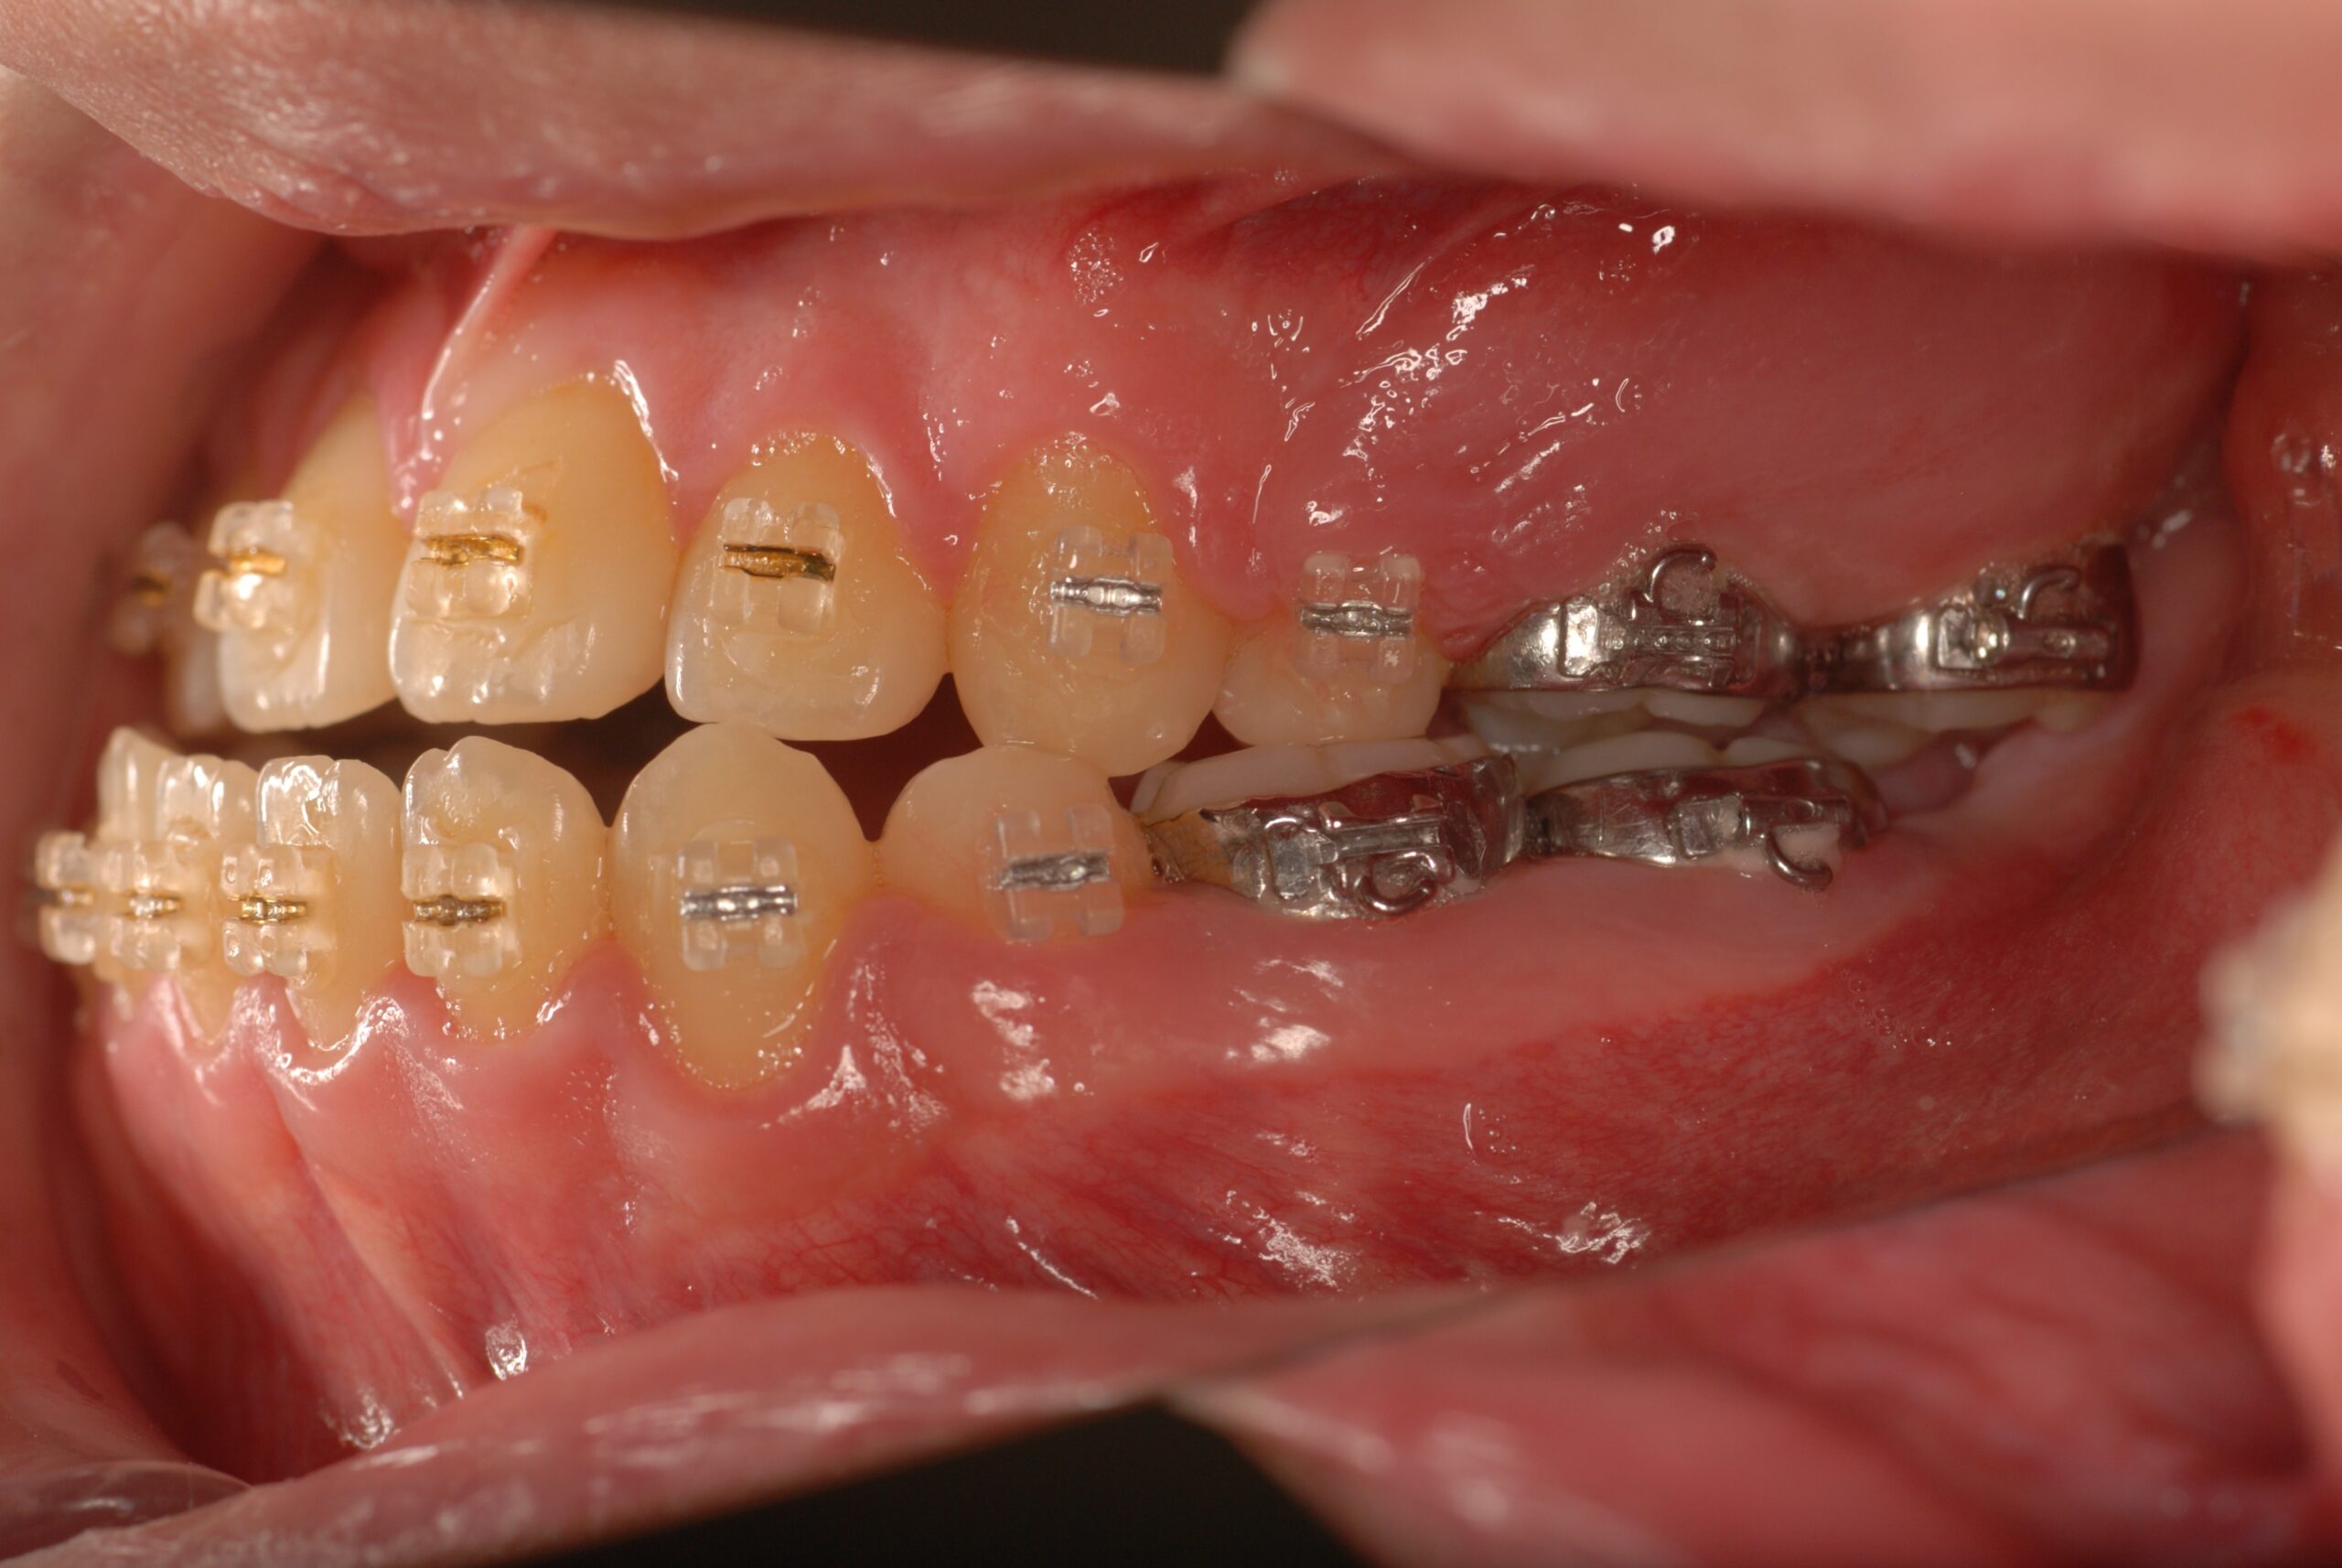

反対咬合(受け口、下顎前突) 叢生

Progress

- 骨格性下顎前突症、下顎骨左偏位、叢生、 顎変形症として、外科的矯正術を計画。 叢生、右側第2大臼歯鋏状咬合。 上下顎第一小臼歯を抜歯し、抜歯空隙を利用し叢生を改善し、上下顎それぞれ歯列を整列し、矯正治療中に病院歯科口腔外科にて外科手術(近郊の病院歯科口腔外科にて、口の中から手術、2週間入院)により下顎骨の後退と左偏位の改善をし、適切なオーバージェット、オーバーバイトを付与する。